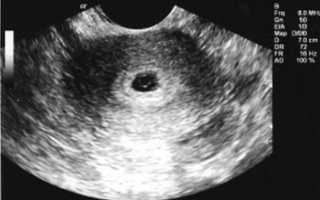

УЗИ: пышный эндометрий — беременность

Пышный эндометрий – это утолщенный функциональный слой эндометрия, который часто сигнализирует о беременности. Вместо того, чтобы отторгнуться и выйти во время менструации, эндометрий утолщается, количество кровеносных сосудов увеличивается, создавая благоприятные условия для существования эмбриона. Эндометрий утолщается к концу цикла в любом случае, а затем либо отторгается, либо помогает эмбриону, вышедшему из яичника, закрепиться в матке и обеспечивает его питанием и защитой.

Пышный эндометрий не имеет симптомов, увидеть его можно во время УЗИ еще до того, как начнет просматриваться само плодное яйцо. Маленький эмбрион может прятаться в этом пышном эндометрии.

Пышный эндометрий при беременности чаще всего указывает на ранние сроки, однако причины могут быть и иные. На таких ранних сроках, когда плод еще не виден (3 недели после зачатия), УЗИ не может гарантировать 100% точность. Врач после УЗИ советует чуть подождать и сделать тест на беременность или же сдать кровь на определение уровня ХГЧ. Если тест отрицательный, следует продолжить обследование и выявить причины увеличения клеток эндометрия.